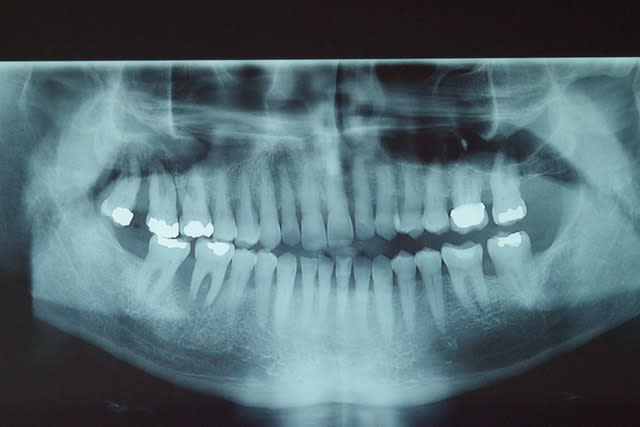

Voilà maintenant les radios:

1° à nouveau une panoramique ( un peu plus haute mais on ne voit pas très bien les ATM )

A priori je ne pense pas que ce patient souffre de luxation au vu des radios.

Qu'en pensez-vous ?